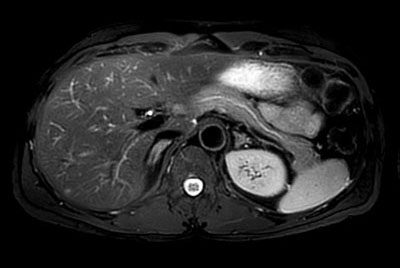

Kidney imaging – Free breathing